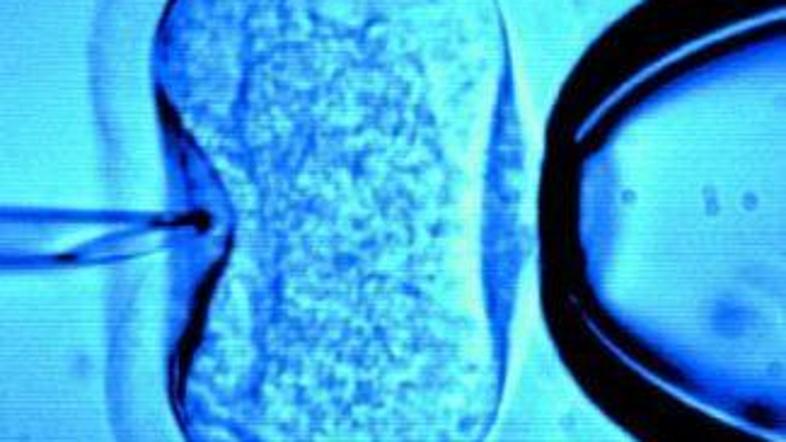

oploditev_250708 Žurnal24 main

Kot je znano, je Nobelovo nagrado za medicino letos prejel britanski doktor Robert G. Edwards za svoje pionirsko delo na področju umetnega oplojevanja. Predsednik Papeške akademije za življenje Ignacio Carrasco de Paula je izbor nagrajenca označil kot "popolnoma neprimernega“, poroča italijanska agencija Ansa.

Odbor za Nobelove nagrade je izbiro utemeljil s pojasnilom, da je prispevek Roberta G. Edwardsa v medicini neprecenljiv, saj je omogočil rojstvo otrok okrog 10 odstotkom vseh parov po vsem svetu, s pomočjo umetne oploditve se je od leta 1978 rodilo okrog 4 milijone otrok.